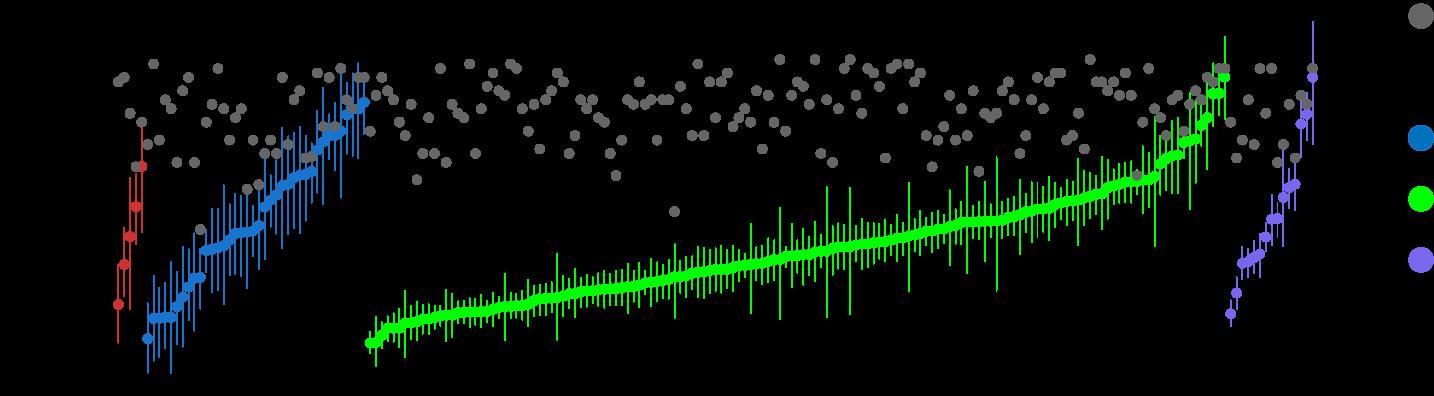

DVRd-Exponential

VRd-Exponential

PERSEUS ITT

DVRd - PERSEUS ITT

VRd - PERSEUS ITT

CEPHEUS TIE

DVRd - CEPHEUS TIE

VRd - CEPHEUS TIE

Estimated PFS, DVRd vs VRd PERSEUS: 205 months (17.1 yrs) vs 87 months (7.3 yrs)

CEPHEUS: 100 months (8.3 yrs) vs 53 months (4.4 yrs)

MRD-negative

Median: 61.9 vs 34.4 months

60-month PFS rate: 52% vs 30% (P<0.001) 5-year rate: 63% vs 45% (P<0.001) 24-month rate: 85% vs 80% 54-month rate: 68% v. 50% (p<0.001)